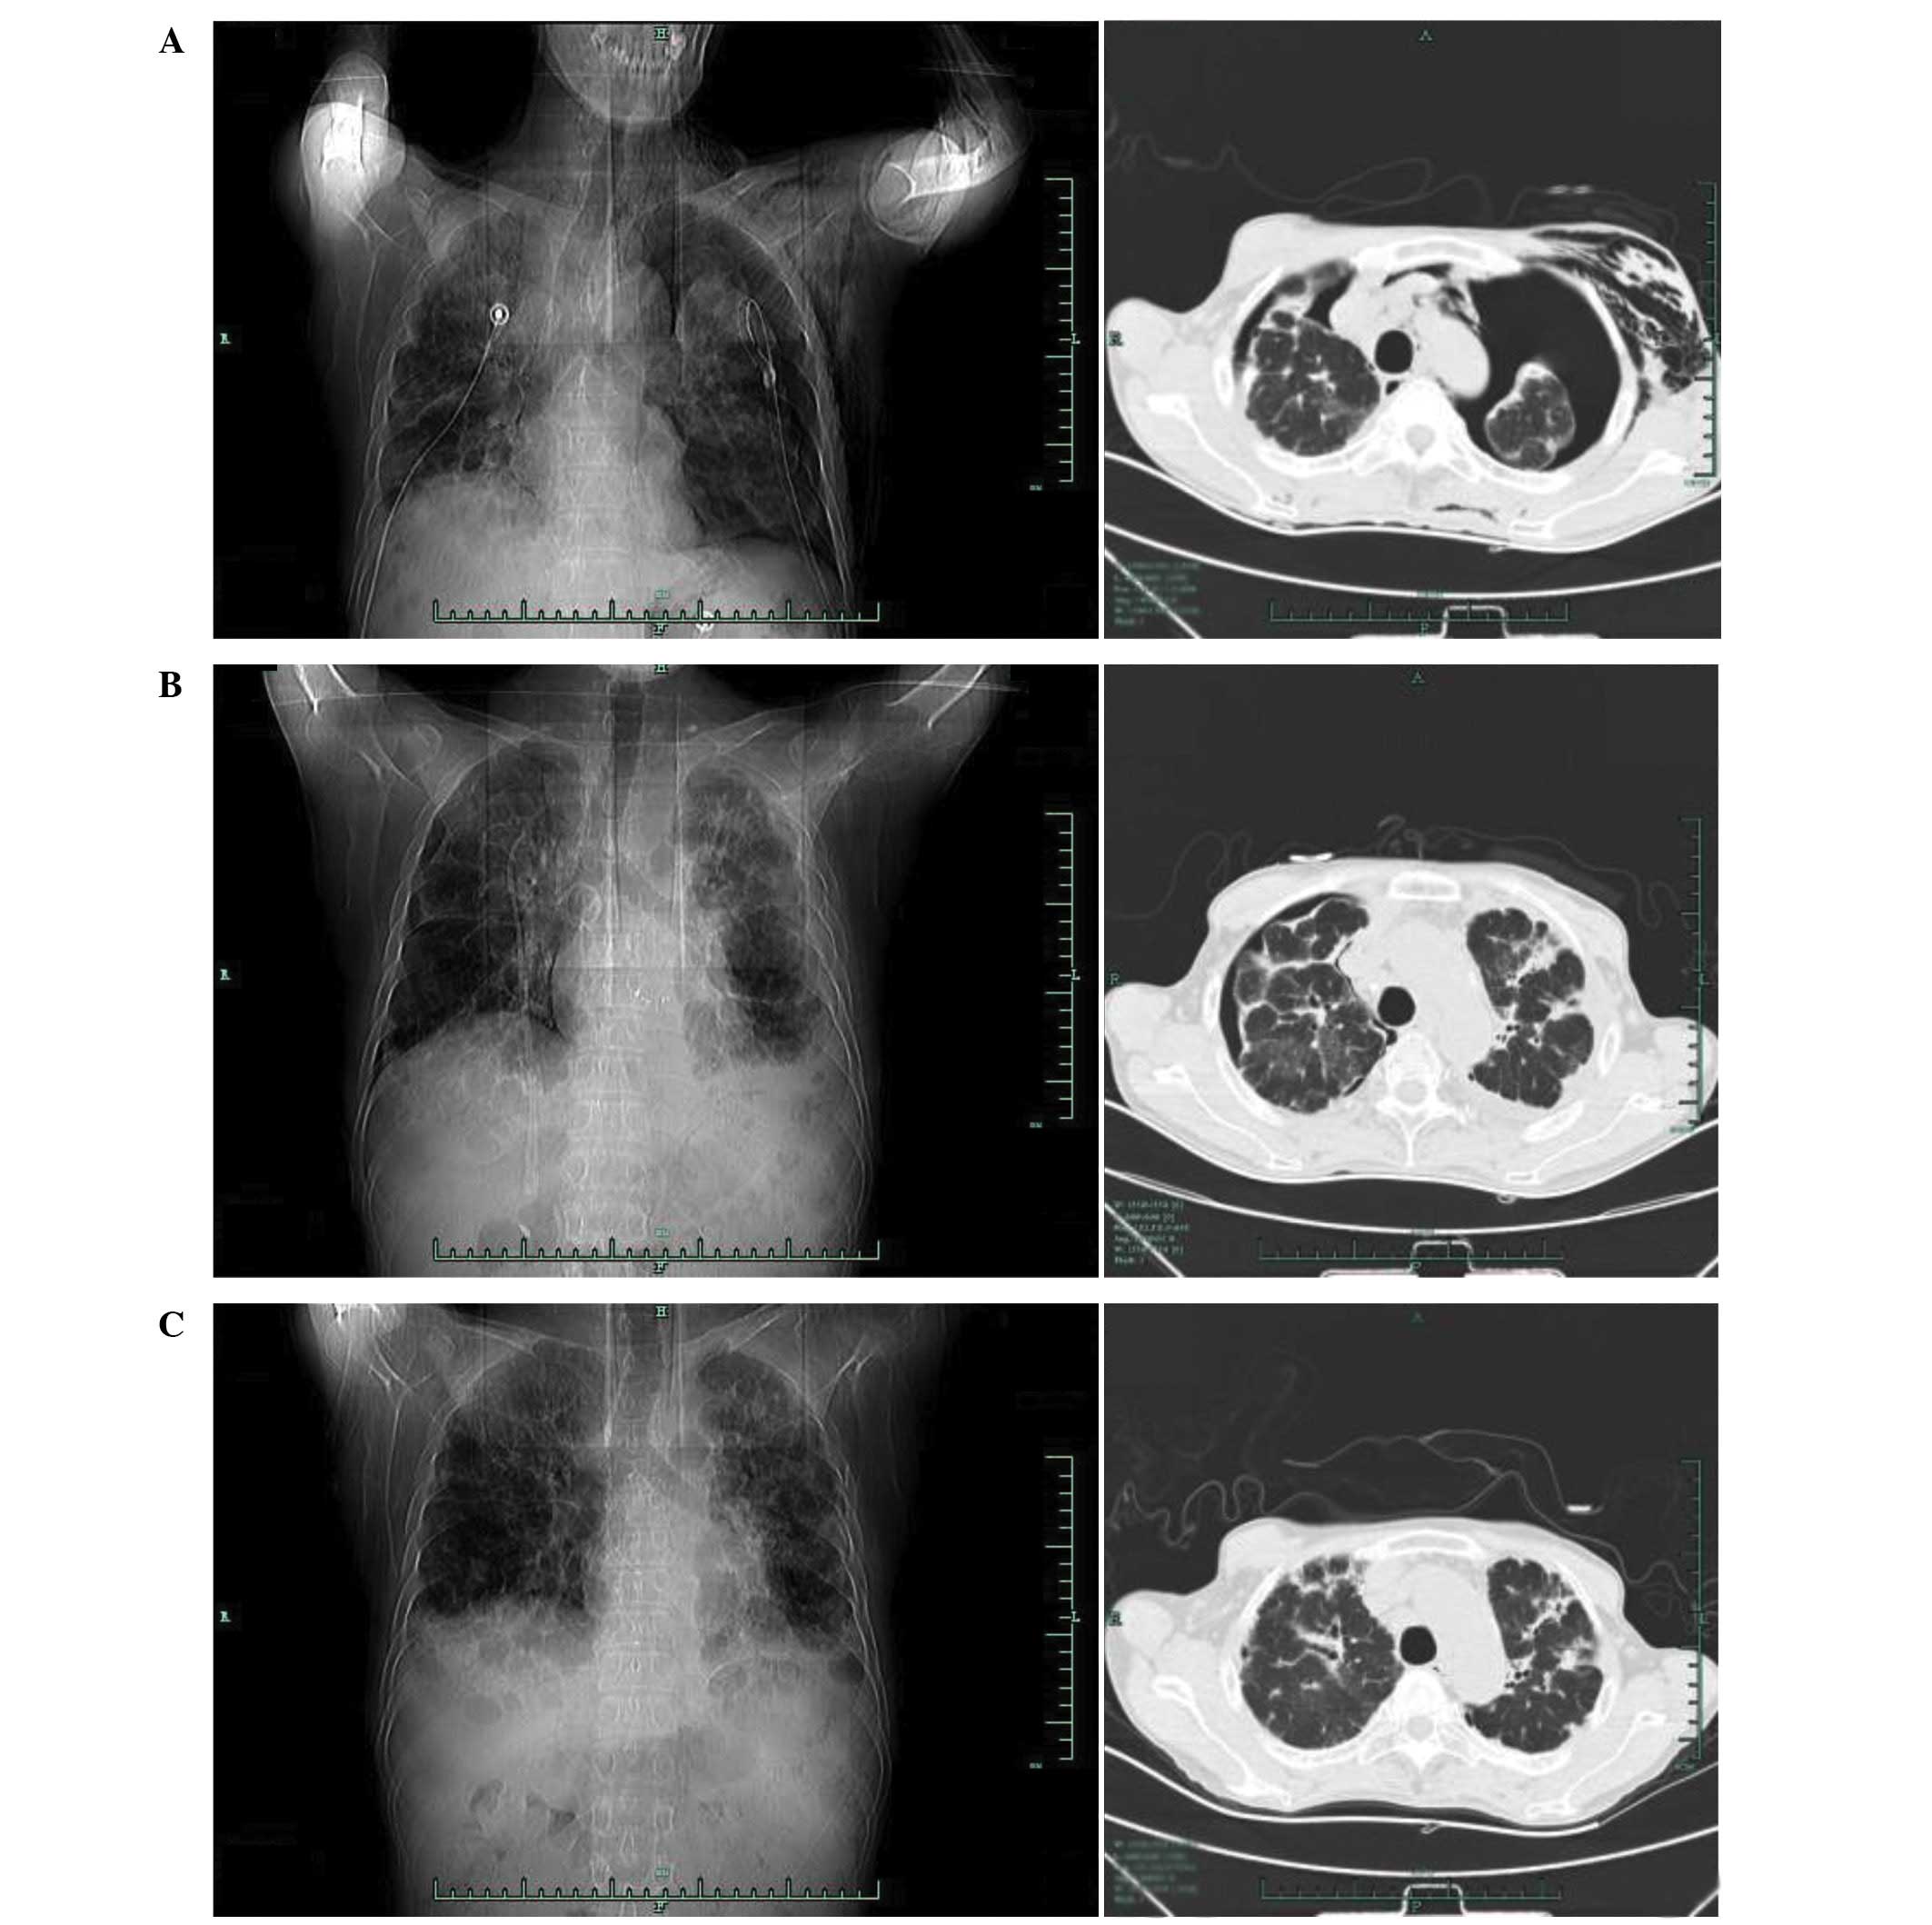

Ipsilateral pneumothorax after ICD placement. Anteroposterior chest

Source: www.researchgate.net

Ipsilateral pneumothorax after ICD placement. Anteroposterior chest, Icd 10 code for primary spontaneous pneumothorax.

Peripheral Tcell lymphoma unspecified type presenting with a

Source: www.spandidos-publications.com

Peripheral Tcell lymphoma unspecified type presenting with a, Available for iphone, ipad, android, and web.